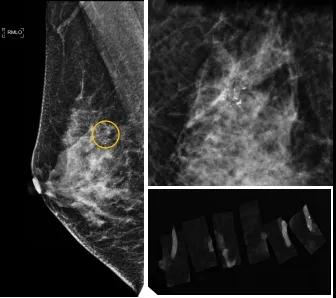

小到1—2mm的鈣化也能活檢!西安國際醫學中心醫院采用精準技術讓乳腺早癌無處可逃

46歲的某女士在西安國際醫學中心醫院體檢時,行乳腺X線攝影(俗稱鉬靶)發現右乳可疑簇狀鈣化,分布范圍不到1厘米,臨床觸不到,超聲很難發現,但是這種鈣化風險比較高,依據國際BI-RADS指南需要明確病理!

西安國際醫學中心醫院影像診療中心陳寶瑩副主任帶領的團隊,采用全數字化乳腺X線三維立體定位系統可實施。這個團隊的成員大部分來自知名三甲醫院,有著十余年影像引導下乳腺介入診療的經驗,X線引導穿刺定位和活檢例數居西北前列。為減少患者創傷,在詳細判讀了患者資料,并與患者及甲乳外科劉曉敏主任充分溝通的基礎上,團隊確定采用全數字化乳腺X線三維立體定位系統下實施粗針活檢。

當天,乳腺X線三維立體定位系統清晰顯示出了所有鈣化。為了獲取充足的組織量,保證病理診斷的準確性,團隊選用14G穿刺針并多點、多角度取材,組織取出后,又立即在高清標本攝影系統中進行投照,從而確定了取出組織中具有足夠的可疑鈣化。整個過程患者無任何不適,活檢結束后即回家觀察。

后期病理回報活檢組織條中均查見導管原位癌。該女士及家屬對西安國際醫學中心醫院早期發現并精準確診病變的技術給予了高度的贊揚。

乳腺導管原位癌屬于早期的腫瘤性導管內病變,有發展為浸潤性癌的傾向,需要早發現早治療,其預后明顯優于浸潤性癌。2020年癌癥雜志的文章指出,近90%的導管原位癌僅表現為不可觸及的可疑鈣化,乳腺X線檢查是發現微小鈣化最敏感的方式,因此70–90%的導管原位癌是通過乳腺X線篩查發現。多年來國內外指南,如美國國家綜合癌癥網絡(NCCN)指南及中國抗癌協會乳腺癌診治指南均建議40歲以上女性每年通過雙乳X線檢查(鉬靶)進行乳腺癌篩查,高危人群建議提前進行篩查(小于40歲)。由于雙乳X線篩查的推廣,歐美等國家導管原位癌的檢出率極大提高,明顯降低了乳腺癌的死亡率。在我國規范進行乳腺X線篩查的人群比例比較低,很多人發現腫瘤時已經為浸潤性癌,因此提醒大家高度重視規范的雙乳X線篩查。通過乳腺X線篩查發現的可疑鈣化需要在X線引導下精準定位,進行粗針穿刺或真空輔助旋切活檢,以獲得準確的病理學結果,給予及時有效的治療。